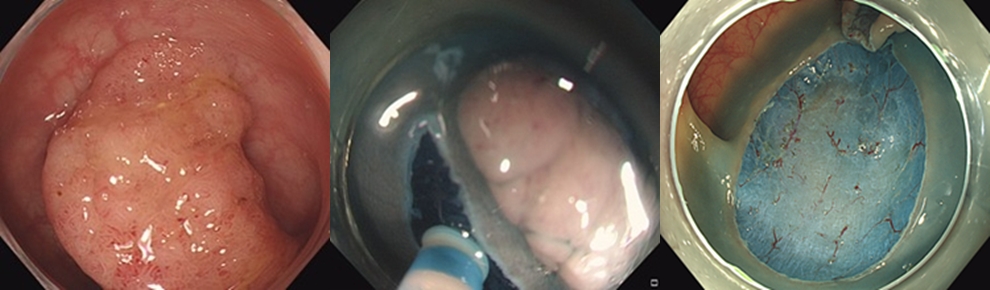

김민준 교수는 ESD를 통해 병변을 한 번에 절제하는 데 성공했다. ESD는 병변 아래 점막하층을 박리해 제거하는 시술로, 개복 없이 병변을 한 번에 제거할 수 있어 회복이 빠르고, 수술을 대체할 수 있는 치료법이다.

시술 후 시행한 병리 검사에서 해당 병변은 조기 대장암으로 판명되었다. 실제 암 크기는 0.5cm였으며, 선종(암 전 단계 포함)은 3.0cm였다. 큰 용종(선종) 안에 아주 작은 암이 포함된 상태였다. 다행히 암세포의 침윤 깊이가 얕아 내시경 시술만으로도 충분한 치료 효과를 거둘 수 있었으며, 추가적인 개복이나 복강경 수술 없이 완치 판정을 받았다. 환자는 현재 특별한 후유증 없이 일상에 복귀했으며, 연 1회 정기 검진을 통해 체계적인 사후 관리를 받고 있다.